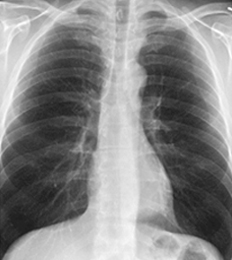

DxRAD는 인공지능기반 흉부 X-ray 의료영상진단보조장치로서,

흉부 X-ray를 촬영 후 분석 및 판별 결과를 DxRAD에 저장 및 각 과에서 열람이 가능합니다.DxRAD는 정상, 비정상, 결핵이 판별가능하며, 의료기기품목 3등급에 해당합니다.전체 병원의 70%에 영상의학과 전문의가 부재 또는 부족하며 의사의 판독정확도는 활동성 51.4%, 비활동성 62.2% 일치하고 있습니다.결핵은 법정 전염병 2군에 해당 하여 진단과 동시에 격리를 해야 하며, 조기진단이 필수인 질병입니다.DR, CR, Film이 가능하기 때문에 오프라인 및 온라인에서도 사용할 수 있습니다.타겟시장으로는 보건소, 보건지소, 개인 병∙의원 등 입니다.